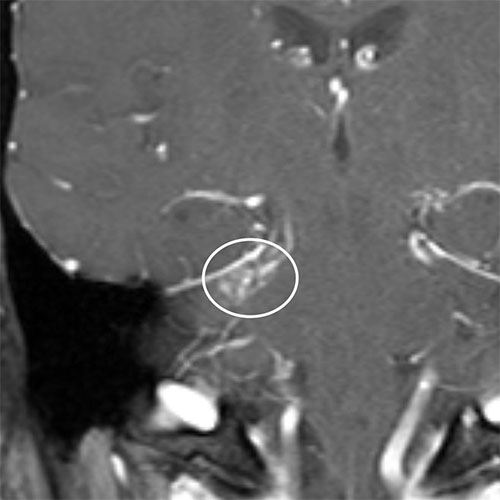

Asymmetric enhancement was questioned on a coronal T1W contrast enhanced MRI in a 34-year-old man with right sided pulsatile tinnitus. The patient underwent catheter angiography which confirmed a small right cerebellar arteriovenous malformation treated with stereotactic radiosurgery (SRS).